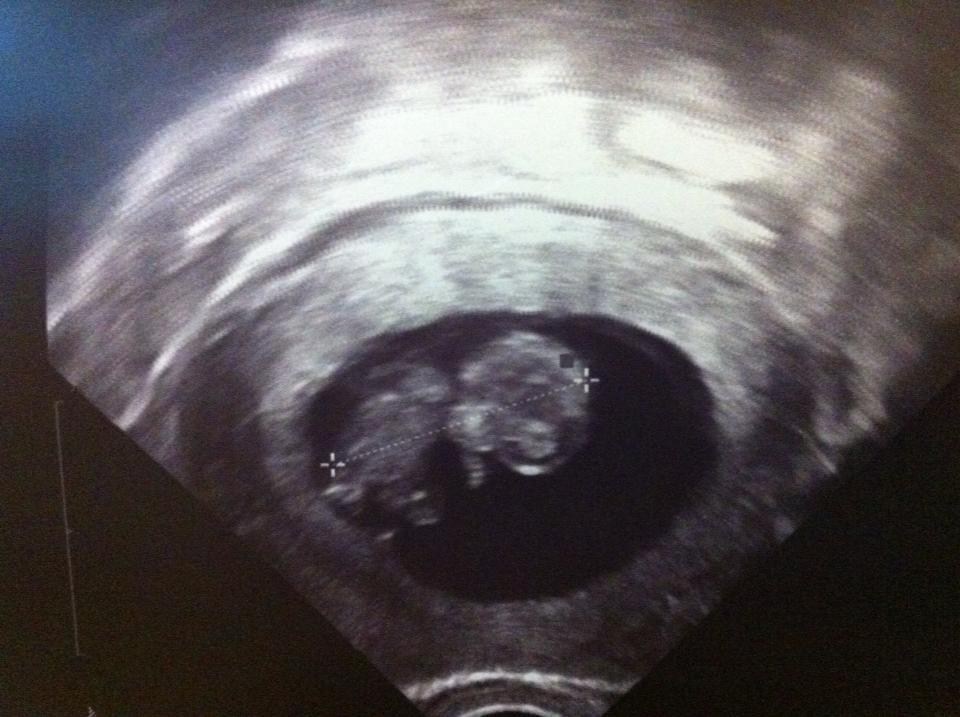

så nåede jeg 9+6 (10uge) og var idag til kontrol tjek grundet vandcyste på højre æggestok (den er blevet mindre JUBIII

), og bebs er blevet større...... EN DEL STØRRE SIDEN SIDST

Nå men vil bare lige vise jer scanningsbilledet